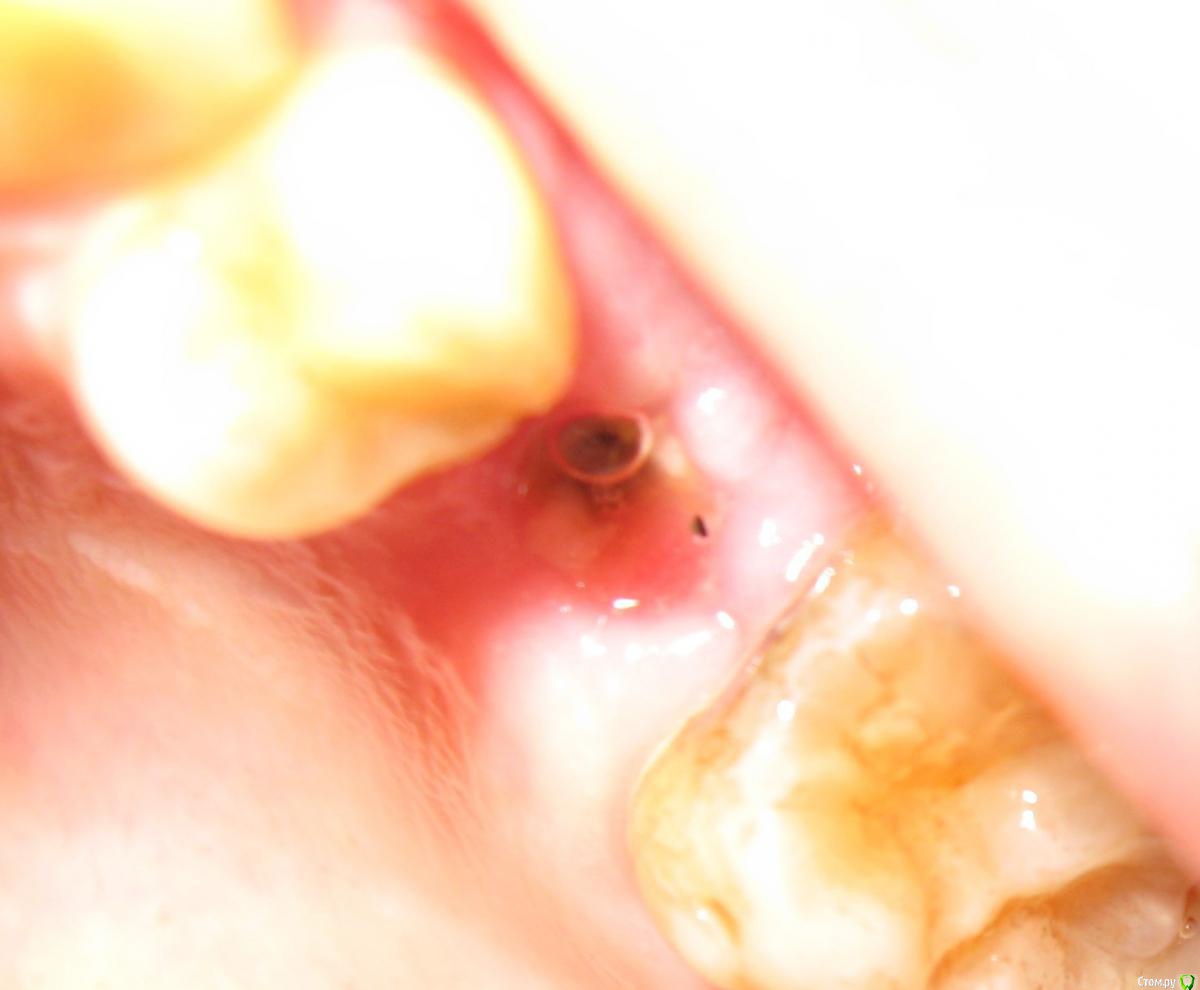

Natalia_ Опубликовано 4 апреля, 2015 Поделиться Опубликовано 4 апреля, 2015 Уважаемые специалисты,посмотрите, пожалуйста, стоит мне из-за этого беспокоиться или не все так страшно. 2 недели назад имплантация, 5-ка, вчера сняли швы - и я вижу имплант над десной..(Под швами не знаю что было, не приглядывалась) Вроде так не должно быть? Будет заметен абатмент потом над коронкой (и портить мне настроение), если так оставить? Чего с ним делать - удалять и переделывать или не все потеряно. Что посоветуете? Переделывать страшно, но чтобы видно было - не хочу... Ссылка на комментарий

Natalia_ Опубликовано 6 апреля, 2015 Автор Поделиться Опубликовано 6 апреля, 2015 Была сегодня у хирурга. Говорит, все у меня хорошо, швы не разошлись, никакой имплант наружу не торчит, десна еще будет зарастать, и поменьше надо в рот смотреть. Озадачена. Видно же имплант? Резьбу блестящую вчера видела. (Сейчас синей мазью замазано после осмотра). Ну, я конечно, рада, если у меня все хорошо ... Подскажите, пожалуйста, уважаемые специалисты-имплантологи, вы кто-нибудь вот так импланты оставляете? Зарастет он у меня или так останется? (или десна наоборот просядет?) Ссылка на комментарий

Aquarius Опубликовано 6 апреля, 2015 Поделиться Опубликовано 6 апреля, 2015 Так мне говорят, что не разошлись швы-то...( И формирователь ставить не собираются. Говорят - так ходить...Я ж сама себе не зашью и не поставлю. И другой хирург вряд ли возьмется. Может там действительно торк этот маленький и вылетит все к .Конечно Ваши фото не показательны. Но мажьте на всякий случай метрогилом плюс солкосерил дентальный. Похоже,что и само закроется. Ссылка на комментарий